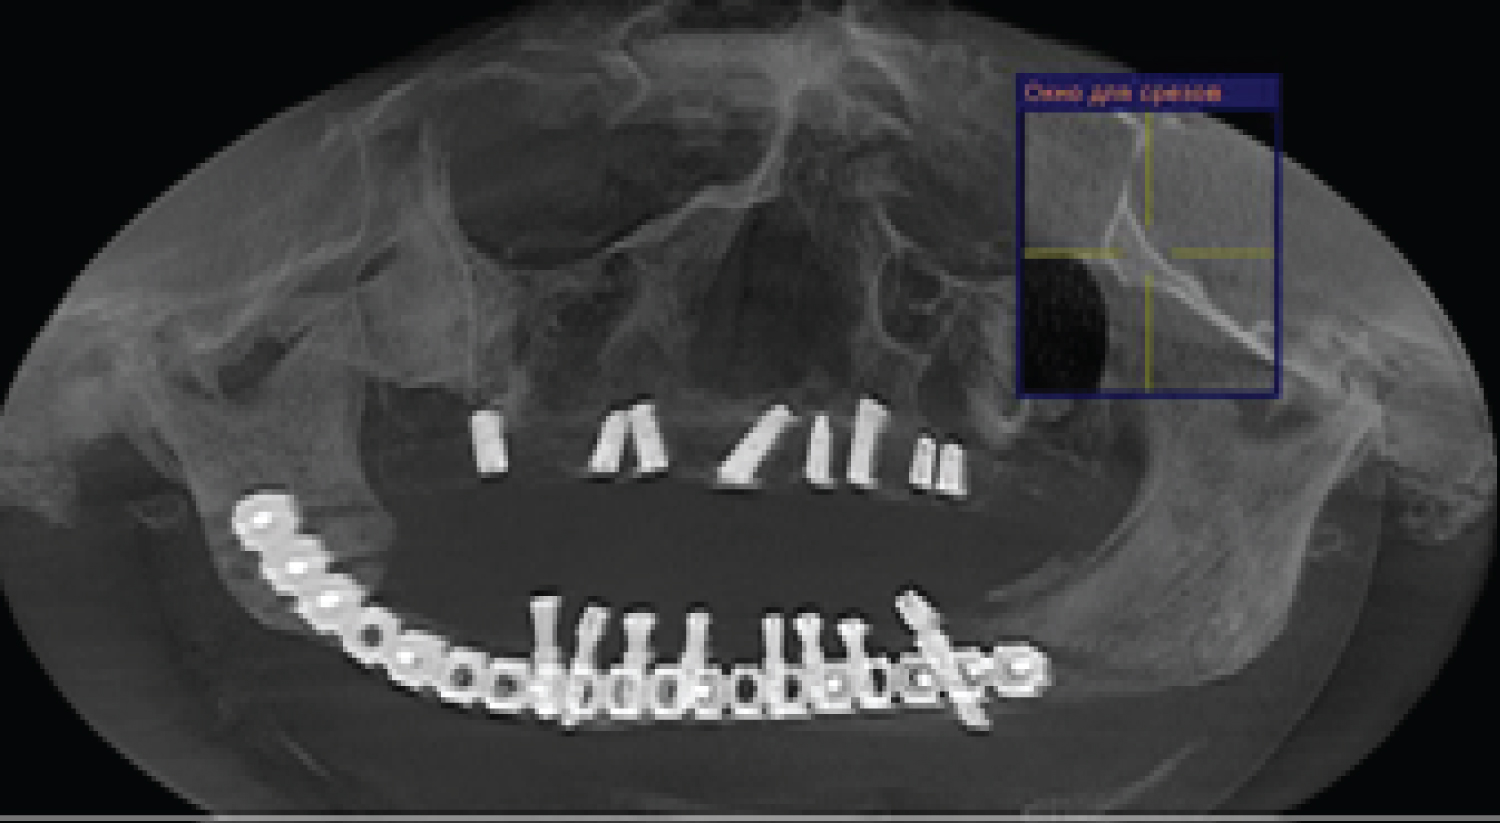

To assess the degree of osseointegration and determine the timing of the functional load of dental implants installed in free vascularized bone autografts, a Resonance-Frequency Analysis (RFA) of the stability of implants using Osstell Mentor (Osstell instrument, Integration Diagnostics AB, Gothenburg, Sweden) at time of implant placement, after 3 months. All patients presented functional and esthetic complaints. All patients underwent a thorough clinical laboratory, radiological examination according to a generally accepted scheme. Patients were evaluated by preoperative and postoperative outcome using computed tomography scan evaluation using CT Galileos (Sirona, German) (Figure 2, Figure 3, Figure 4, Figure 5 and Figure 6). Biopsy of the lesion was obtained in all cases. The choice of surgical treatment is determined by the type of lesions and the sizes of jaw defect.

Figure 3: (Patients 1) CT scan after fibula transplant surgery. View Figure 3